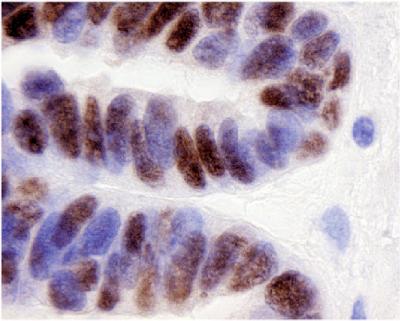

A new study suggests that ovarian cancer cells form by hijacking a developmental genetic process normally used to form fallopian tubes. Scientists at the Georgia Institute of Technology and the Ovarian Cancer Institute discovered that the protein, PAX8, is involved in the development of fallopian tubes and is present in ovarian cancer cells, but not in normal ovarian tissue. The discovery not only provides a new target for diagnostic and therapeutic interventions, but also opens new avenues for basic research in ovarian cancer pathology. The research appears in Volume 104, Issue 3 of the journal Gynceologic Oncology.

In 2003, a group from Stanford University researching breast cancer discovered that paired box gene 8 is expressed in ovarian cancer tissue, but not in breast cancer. Taking note of the Stanford group's results, OCI researchers began to investigate the possibility that the gene and its products may be an important biomarker for detecting and researching the causes of ovarian cancer. They began to look for evidence of PAX8, the protein made by paired box gene 8, which was the next step in establishing the gene as a biomarker. Not only did they find PAX8 in the ovarian cancer cells, but they also found it in the cells that form fallopian tubes, the secretory cells. In addition, they discovered that the protein is not expressed in the normal ovarian surface epithelium.